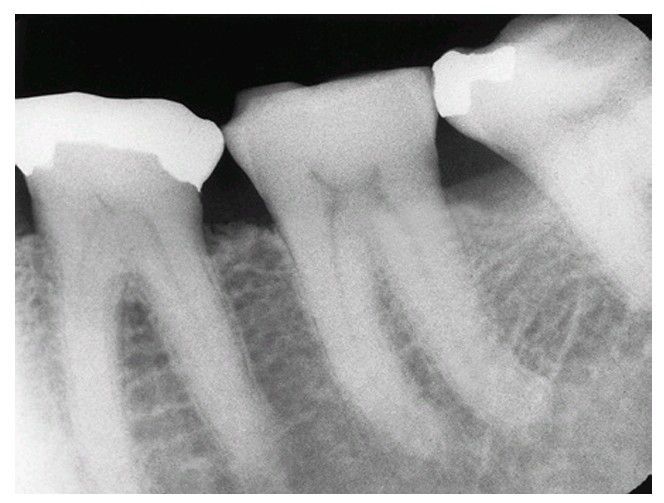

Bruxism

Teeth that exhibit evidence of bruxism may have denser bone and stronger periodontal ligament attachment, which make them more difficult to extract.